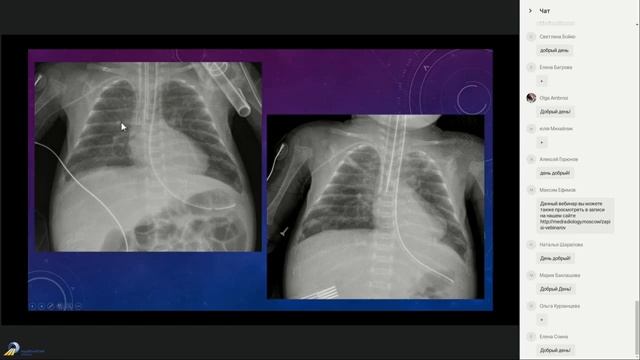

Рентгенодиагностика заболеваний органов грудной полости у новорожденных